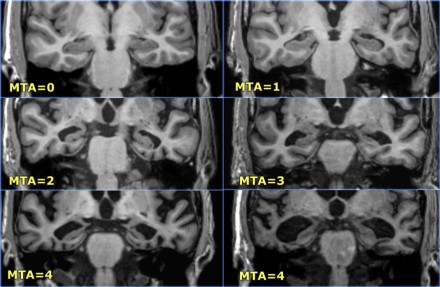

La escala visual de scheltens fue desarrollada para valorar el grado de atrofia del lóbulo temporal, evalua el grado de atrofia en base al análisis visual de tres estructuras – la cisura coridea el asta temporal y el hipocampo – en el plano coronal de la secuencia 3D volumetrica. Esta escala permite distinguir entre pacientes con EA y de edad avanzada.